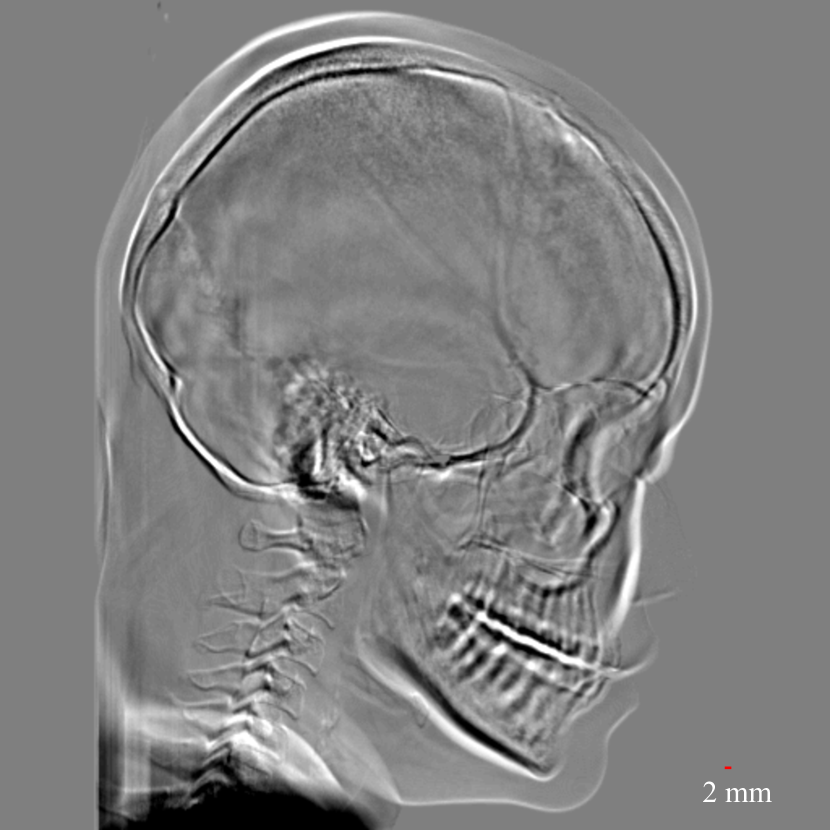

Figure 11: Perspective deformation learning in one exemplary patient case for cephalometric imaging. In (b), the left and right sides of the mandible do not overlap well, as indicated by the arrow. In (c), a scale bar of 2 mm is displayed (zoom in for better visualization), as 2 mm is the clinically acceptable precision for cephalometric landmark detection. In (e), (h) and (j), incorrect areas are marked by the red arrows.

The results of one exemplary patient for cephalometric imaging are displayed in Fig. 11. In the 0superscript00^{\circ} perspective projection image (Fig. 11(b)), because of perspective deformation, anatomical structures from the left and right sides do not overlap well, especially for the mandible as indicated by the red arrow in Fig. 11(b). It causes inaccuracy in determining the cephalometric landmark of the gonion. The difference of Fig. 11(b) to the reference Fig. 11(a) is displayed in Fig. 11(c). A scale bar of 2 mm is displayed in Fig. 11(c), as 2 mm is the clinically acceptable precision for cephalometric landmark detection. It is obvious that many anatomical structures in the 0superscript00^{\circ} perspective projection images have position shifts larger than 2 mm. In the prediction image (Fig. 11(d)) using a single 0superscript00^{\circ} view in Cartesian coordinates, perspective deformation is reduced to some degree, as displayed in the difference image Fig. 11(g). For example, the mandible region has less error. However, Fig. 11(g) also indicates that many bony structures still have deviations larger than 2 mm. The results of learning from dual complementary views in Cartesian and polar coordinates are displayed in Fig. 11(e) and Fig. 11(f), respectively. Both images have little perspective deformation, as revealed by their difference images in Fig. 11(h) and Fig. 11(i). Nevertheless, in Fig. 11(e), two dark regions are indicated by the two arrows, which are better visualized in the difference image Fig. 11(h). The results of TransU-Net are displayed in Figs. 11(j)-(o). In Fig. 11(m), the structures near the porion landmark are distorted, for example, the ear canal indicated by the arrow. Consistent with Pix2pixGAN, perspective deformation is largely reduced in the both TransU-Net prediction images using dual complementary views in Cartesian and polar coordinates.